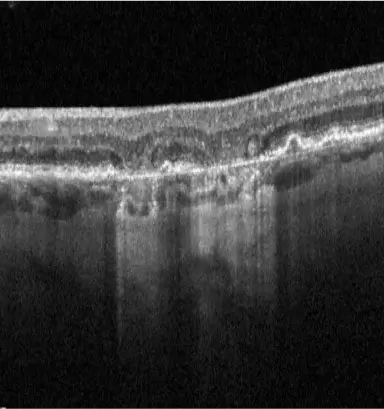

IZERVAY™ (avacincaptad pegol intravitreal solution) is indicated for the treatment of geographic atrophy (GA) secondary to age-related macular degeneration (AMD)